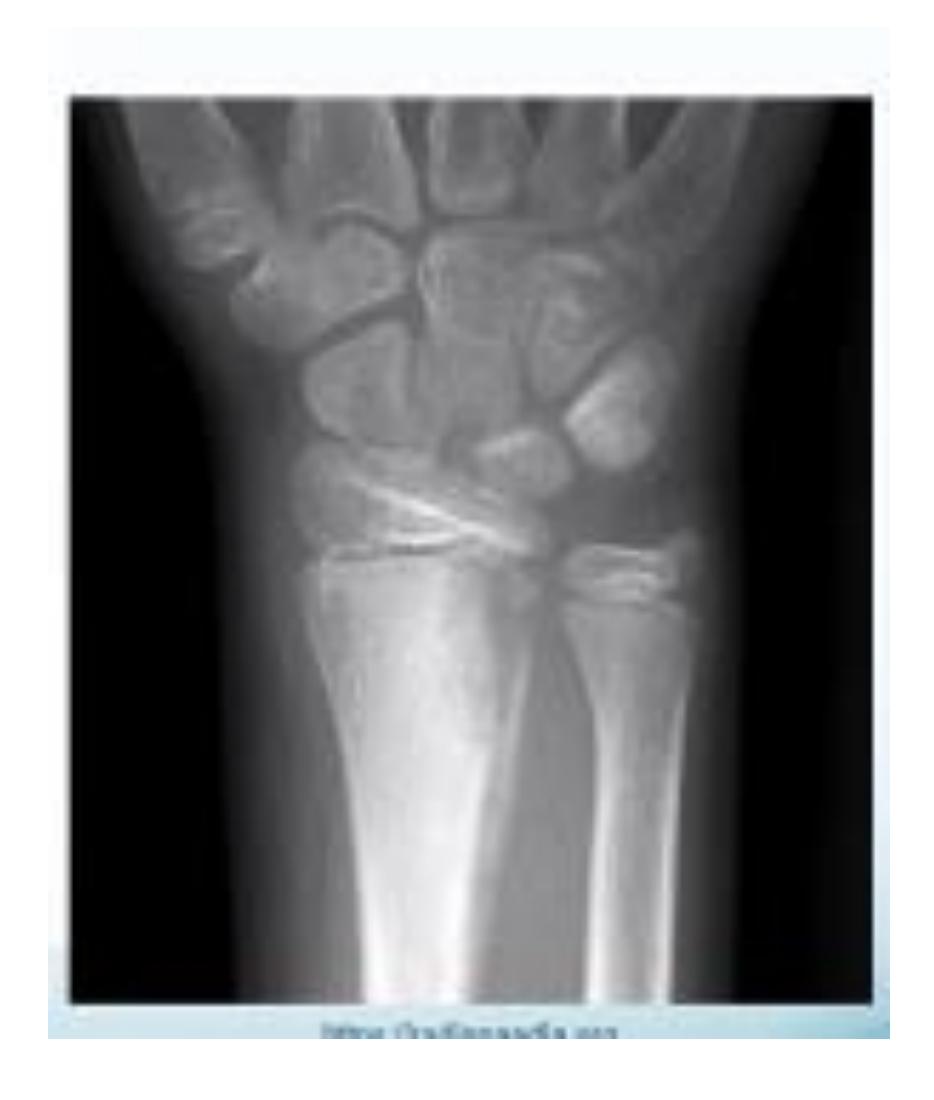

Wrist and Hand Fractures

Collesโ Fracture

- Deformity: Dinner-fork deformity

Scaphoid Fracture

Scaphoid Fracture Treatment

- Treatment: Thumb spica cast